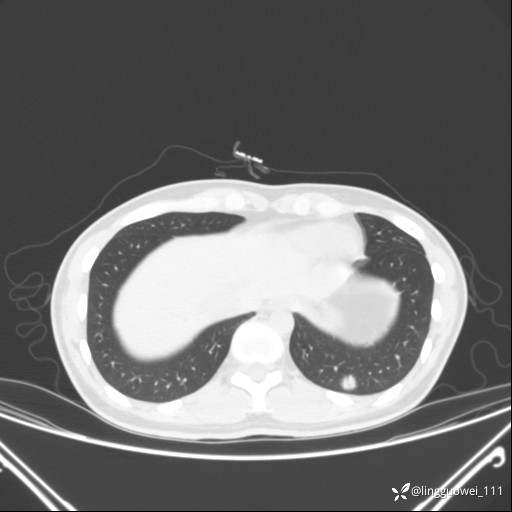

患者性别:女

患者年龄:26岁

主诉:咳嗽来诊,结节性质不明。

肺毛细血管瘤 (2)